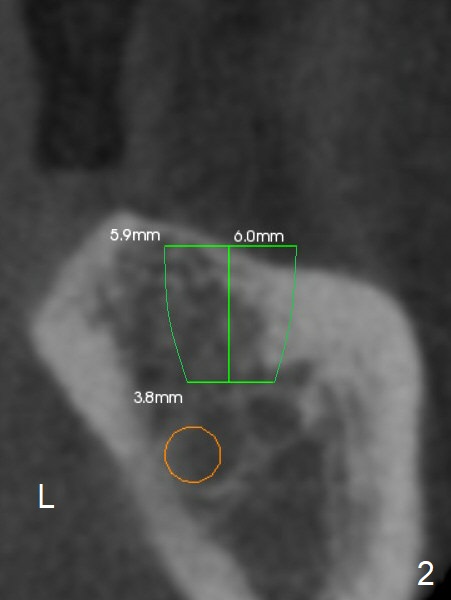

A 57-year-old man has severe bone loss at #18 (Fig.1). It appears that there are 3 sites of placement of an implant (Fig.2,3).